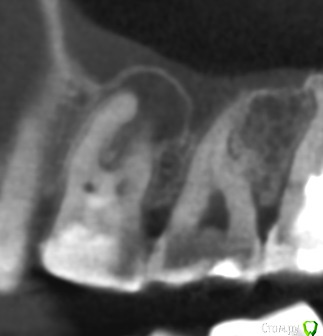

vse32 Опубликовано 6 ноября, 2019 Поделиться Опубликовано 6 ноября, 2019 Я стоматолог терапевт, поэтому вопрос почти как от обывателя.16 зуб, женщина около 35 лет (не видела ее, коллега мужа по работе). В сторонней клинике сделали ОПТГ и КТ и рекомендовали удаление с одномоментной имплантацией. Со слов женщины предложен корейский имплантат за х рублей + подсадка за х рублей. Или американский имплантат за 2х рублей без подсадок.Вопрос - нормально ли это делать одномоментно при наличии кистогранулемы (вне обострения).Лечить эндодонтически могу, но сомневаюсь в гарантийности работы. Ссылка на комментарий

колесников Опубликовано 7 ноября, 2019 Поделиться Опубликовано 7 ноября, 2019 (изменено) всё возможно в этой жизни. Интересно посмотреть такой кейс. Но это смущает а что Вас смущает? Ситуация очень благоприятная,киста сама сделала синуслифтинг,если сделаем паузу-потеряем этот объём Изменено 7 ноября, 2019 пользователем колесников 4 Ссылка на комментарий

колесников Опубликовано 10 ноября, 2019 Поделиться Опубликовано 10 ноября, 2019 Какой протокол имплантации в таком случае, как быть уверенным что инфекции не осталось в полости с гноем? Как вообще правильно? Удалить, обильно промыть эндошприцем, крутить с графтом или без? Кюретажить или нет? ну ладно пациенты,но Вы то! Какой гной! Где? Вылущили оболочку-все чисто. Обычно и вылущивать ничего не нужно,вынули зуб ,а на нем висит оболочка. Ревизию по стенкам конечно лучше делать и промыть. Грануляции от жидкости набухают и визуализируются. Лунка под капсулой стерильна. Главное чтобы слюна не попала и не остались грануляции. Я всегда использую графт,тк такой объём сгусток не в состоянии сохранить,распадётся. 1 Ссылка на комментарий

колесников Опубликовано 11 ноября, 2019 Поделиться Опубликовано 11 ноября, 2019 (изменено) Просто лежать в графте на в/ч он не может,силу тяжести никто не отменял. Имплант обязательно должен контактировать с нативной костью и иметь хоть минимальную ,но стабильность. Стабильность,как ответили выше ,можно получить зацепившись апексом за свод, где то за перегородку,и фдм иногда помогает. Были случаи стабильности только от супраструктуры и имплант интегрировался.Это не просто идея и красивое фото,это вполне себе рабочая модель Изменено 11 ноября, 2019 пользователем колесников 4 Ссылка на комментарий